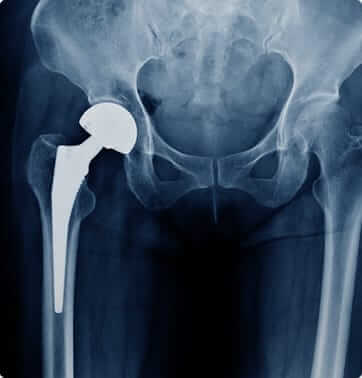

In a total hip replacement, the “ball and socket” parts of the hip and upper thigh bone (femur) are replaced with an artificial implant meant to act and move like your natural hip.

These procedures can effectively eliminate pain and return mobility to people with severe cartilage damage within the hip or knee joint. In both cases, the joint is surgically removed and replaced with a prosthesis.